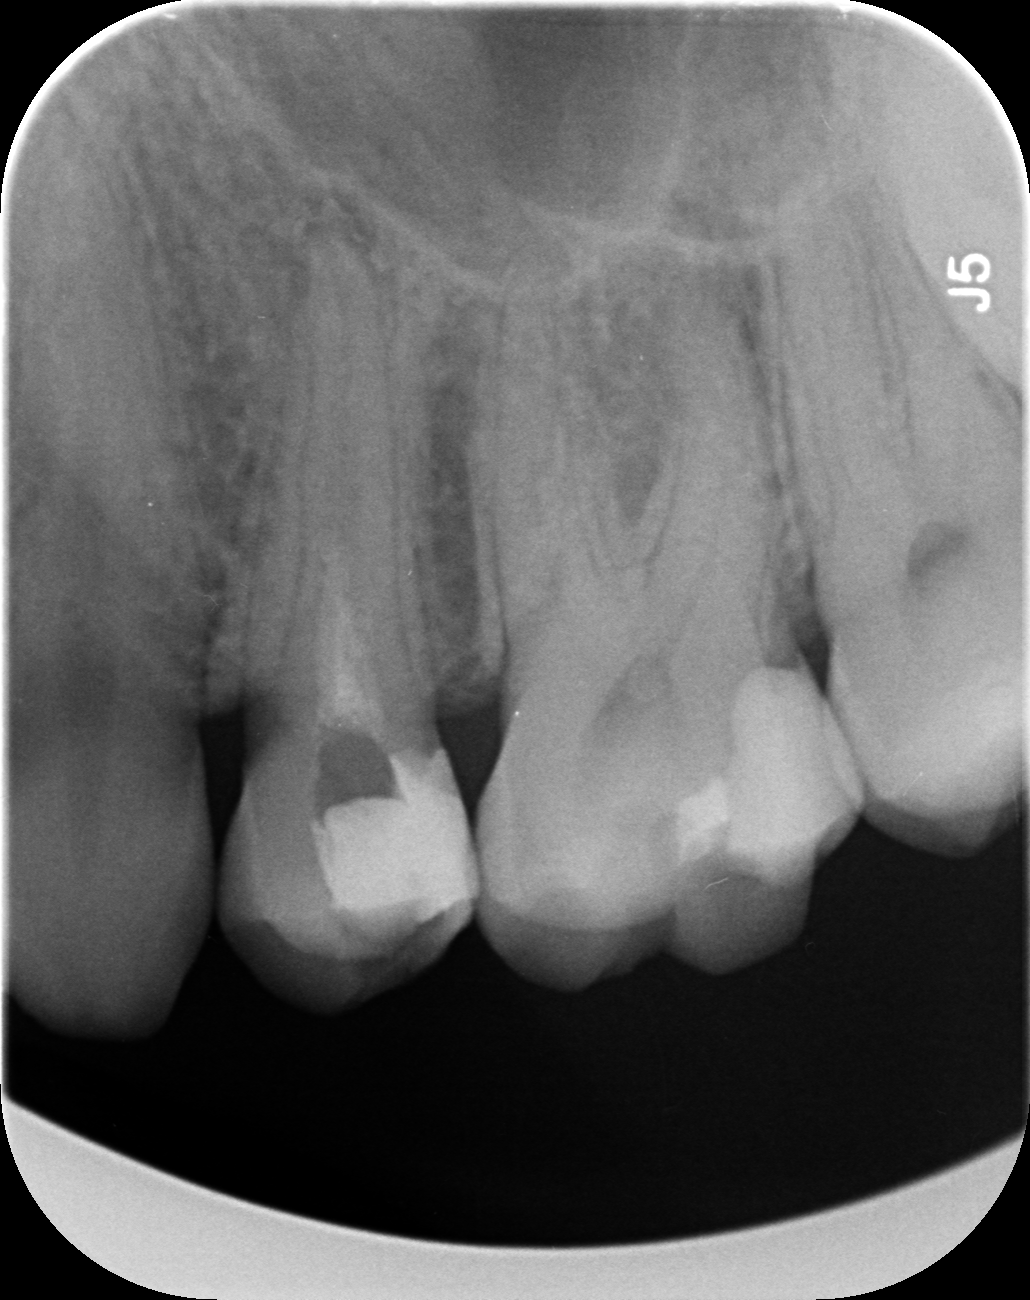

Dantų kanalų gydymas